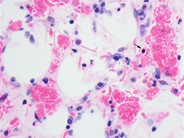

Aplastic Crisis in a Patient with Sickle Cell Disease - 1.

Category: Red Cell: Hemoglobin disorder

Numerous sickled RBC's are present (small arrows). A single nucleated RBC is noted (large arrow). Of note is the absence of polychromasia.